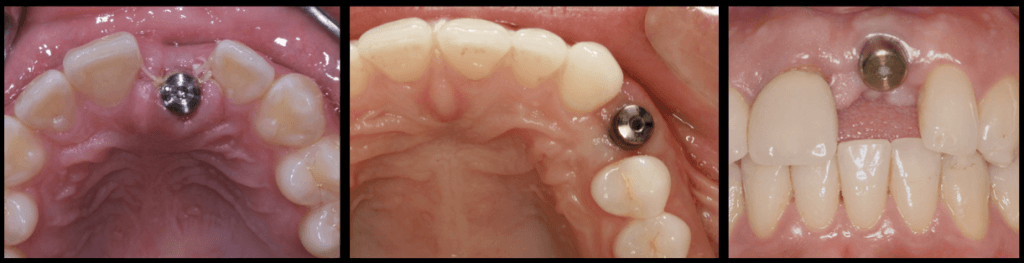

In the supracrestal complex, the roof is the crucial couple of millimetres of the prosthesis slightly above and slightly below the margin of the soft tissues. This is the surface of the prosthesis which first meets the soft tissues and it is crucial because this is where the Biofilm forms. If this is uncleanable, inflammation of the supracrestal complex is only a matter of (short) time.

Nr. 4: Position yourself for success !

The correct 3-dimensional implant position is essential for everything else to work Compromised implant 3D position is the “root of all evil” leading a chain reaction of compromise in the restorative design and finally maintainability. Knowing the limitations from the beginning and decide the strategy that will allow us the perfect placement is an art and a science combined.